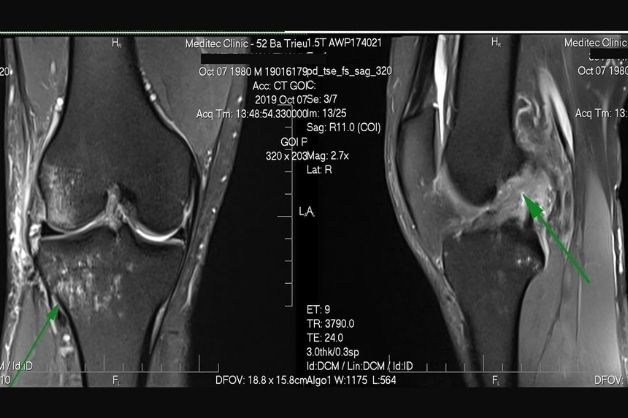

2.6 Chụp xương khớp

Người bệnh thực hiện chụp MRI xương khớp có thể giúp phát hiện sớm các bệnh lý như: thoái hóa chấn thương xương khớp, chấn thương dây chẳng, tràn dịch ổ khớp… Đặc biệt, hình ảnh đem lại từ cấu trúc xương, ổ khớp, gân và dây chẳng qua chụp MRI rất rõ nét, chi tiết, giúp quá trình chẩn đoán và điều trị dễ dàng hơn.

Hình ảnh thu được từ phương pháp chụp cộng hưởng từ ở bệnh nhân gặp vấn đề về xương khớp